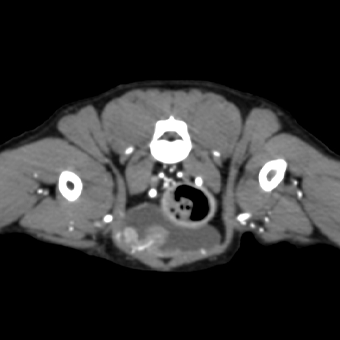

CT 진단 케이스

비강 종양

간 종양

횡경막 탈장

부신 종양

요관결석과 수신증

방광 종양

침샘종

외이염

후지파행

골반골절